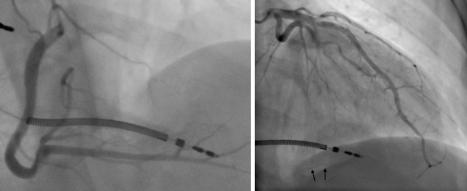

病史摘要:48岁男性患者,2025年10月24日9:40工作时突发意识丧失、小便失禁、呕吐。3年前曾行PCI术,高血压、糖尿病用药不详。 诊疗过程:入院查体神情萎靡、神志模糊等,血压低。心电图提示STEMI,实验室检查多项指标异常。西医诊断为急性前壁高侧壁心肌梗死合并心源性休克(Killip IV级)等,中医诊断为卒心痛(气虚血瘀证)。11:08行冠状动脉造影,对前降支病变处理,术中患

起博心律患者出现胸痛应紧急再灌注?你如何判读

病史摘要:74岁男性,有非缺血性心肌病病史及双心室起搏器植入史。因间歇性胸痛2天,持续4小时,伴大汗、呼吸短促至急诊科就诊。诊疗过程:患者生命体征正常,12导联心电图显示心房感知双室起搏伴室性早搏,符合起搏心律下的Aslanger模式,提示下壁闭塞性心肌梗死。两小时后出现多形性室性心动过速。首次高敏肌钙蛋白I显著升高,被诊断为非STEMI,入院至置管时间20小时。血管造影显示右冠状